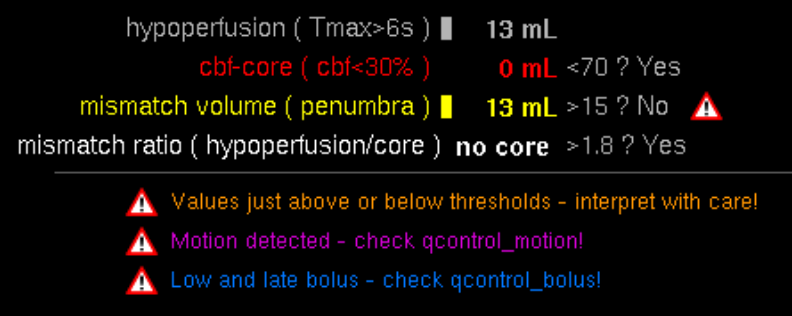

-

As soon as the recording is completed you can click the 'send' button to the receiver.

13.4. Group messages

To communicate with several people at the same time, it is a good idea to create a chat group (see Messaging). The group members can be selected during the creation process as shown in Group member selection.

After the members have been selected, the new group must be named. The name is then displayed to all group members in the overview. See Name group

After confirming the group name the group appears in the messaging overview. You can edit the group settings by clicking the groupname in the top after opening the chat. See Edit group settings. You can assign a profile photo to the group via the "Camera" icon.

14. Screensharing

Screensharing allows you to share your screen with others. After pressing the button (see Chat) the screensharing will start and the image you have already opened will open (see Chat) or you will be redirected to the inbox if no image has been opened yet. The screensharing can be started with one or more persons (see Screensharing in groups), in the form of a group.

In a chat, the administrator is the one who starts the screensharing. In a group the administrator is defined previously (see Screensharing in groups).

The upper figure visualizes the following functions:

-

The one who started screensharing is underlined in white, the active participants are displayed in white and the inactive participants of the group are displayed in gray.

-

With the 'Microphone' button, a participant can activate and terminate the voice function (crossed out). The speaking participant is displayed in yellow.

-

The X button ends the screensharing for all participants.

-

Only the administrator can apply tools during the screensharing.

-

Here you can minimize the window.

The upper figure visualizes the following functions:

-

By clicking the 'green checkmark' button, the participant can join the screen sharing.

-

The administrator is underlined in white, the active participants are displayed in white and the inactive participants of the group are displayed in gray.

14.1. Screensharing in groups

In a group, screen sharing can only be started by a previously determined administrator. For the other participants of the group, the screen sharing starts automatically. In a group only the group administrator can use the voice function.

The upper figure visualizes the following functions:

-

The X button ends the screensharing for all participants.

-

Only the administrator can apply tools during the screensharing.

-

The one who started screensharing is underlined in white, the active participants are displayed in white and the inactive participants of the group are displayed in gray.

-

The number of active participants and all group members.

15. Photo documentation

|

The photo documentation feature is expressly not permitted for diagnosis or treatment decisions. This feature isn’t enabled by default. It is only available for evaluation purposes. If you’re interested in taking part of the evaluation, please contact your mbits support staff. |

When the feature is enabled for the current user you’ll see an extra tab for the photo documentation and a button in your inbox to open the camera. By pressing on the camera button (Point 2) you’ll open the camera and be able to capture all the photos you require. A photo documentation workflow will be like the following

-

Take pictures

-

Select photos that should be assigned to a patient or order

-

Select the body part which reflects the content of the photos

-

Select a patient or order

-

Add more information to the photos (key wording)

-

Confirmation

-

Wait a moment for the photos to appear in the inbox

-

Go to the Photo documentation tab

-

Open the Photo documentation camera

15.1. Camera

When you’ve captured all the photos you need press the photo stack (Point 3) to continue to the review process.

-

Shutter button to capture a image.

-

Select desired camera lens (only on devices with more than one camera).

-

Image stack of taken images. Click to return to gallery.

-

Enable, disable or set automatic flash operation.

-

Enable or disable automatic white balance adjustment.

-

Enable or disable automatic exposure adjustment.

15.2. Photo gallery / Review

The review gallery displays all the photos that you have taken so far ordered by their capture date.

-

Navigation bar shows current progress and allows you to go to a step by tapping on it. By doing that you can only go to a previous step

-

Select button to enter image selection mode.

-

Click on a thumbnail in order to view a image.

-

Click on a thumbnail to add the image to the selection.

-

Button to select a row of images.

-

Cancel selection mode.

-

Deletes the selected images. Deleted images can not be restored.

-

Confirm selection and go to the next step.

|

Danger

Be careful and do not delete images by accident. Deleted images can not be restored. |

If you want to inspect an image more detailed you can enter the photo view by clicking the target photo. Inside the photoview you get a fullscreen overview of the image. In this mode you can perform all the transform operations that are already known from the regular viewer (panning, zoom). By clicking the next or previous (Point 2) button you can navigate between the images.

-

Go back to the image gallery.

-

Switch between images. You can also use a swipe gesture to move forward / backward in the image stack.

-

Deletes the currently opened image. Deleted images can not be restored.

-

Shows the date and time the image was taken.

15.3. Body part

In the next step you are asked to to select a body part to which the selected photogroup belongs to. The selected body part defaults to "Unspecified" and is displayed in a label (Point 4). To select a body part just press on the human. To switch between front and back view you can press the corresponding button (Point 2). For navigation purposes you it’s displayed which side is left or right (Point 3).

-

Body part selection. Click on a body part to select it.

-

Rotates the body part selection so you can select parts on the front and back of the patient.

-

Shows the correct direction relative to the body part selection.

-

Shows the name of the currently selected body part.

-

Confirm the selection and proceed to the next step.

By tapping on the next button you will continue to the orderview.

15.4. Orderview

In this page all patients and unprocessed orders are displayed. Each order/patient are displayed with the necessary information to identify them (Point 1). To filter all the entries you can use the search field in the top (Point 3). To scan a QR or Barcode you can use the corresponding button below the search field (Point 4).

-

Shows patients that are registered in the system.

-

Shows orders that are registered in the system.

-

Filter input to filter the displayed results.

-

Search patient or order by scanning a bar code containing the patient or order id.

-

Shows when the last update or order id has been made.

-

Add a patient to the system by manually entering the correct information.

By clicking an order/patient you’ll proceed to the confirm. If there is no order and no patient that fits your case you’ll want to add the patient manually with the add patient button (Number).

15.5. Patient form

If you have decided to manually add the desired patient, the following view will open. The required tags for the patient are displayed at Point 1 and setup by your pacs administrator. Make sure to enter the correct information before proceeding to the next step.

-

Input fields for the patient information defined by your PACS.

-

Confirm the input and continue with the next step.

15.6. Confirmation view

In this step you have the ability to review your assigned photos one last time and to add additional tags to the order that can help with identifying the order at a later stage. (The keywording must be configured at the server to be available, please contact your administrator or mbits support)

-

Preview of the added images and patient information.

-

Selection of further tags and information for the order.

-

Confirm inputs and proceed.

15.7. Assigned view

This view is the default view when you press the photo documentation tab in the top. It is an overview that lists all unassigned photos, pending orders and completed orders. By pressing the unassigned photos (Point 1) you’ll proceed into the review gallery where you can assign those photos like already described above. The list of pending orders (Point 1) are the orders that have not yet been confirmed by the server. This can be caused by no internet connection or that the server is still processing those orders. The completed list (Point 2) shows all orders that are known to be completely processed. By pressing the "Clear completed" button (Point 3) those orders are not shown anymore to you.

-

List of pending orders that are uploading or waiting for approval.

-

List of completed orders.

-

Button to clear the list of completed orders.

16. VEOcore

|

Warning

Decisions must never be made based on the VEOcore results alone. The product should only be used by trained medical personnel familiar with the current guidelines and the perfusion measurement technique. It is up to the user to carefully take into account all available patient information and to put the VEOcore results into the proper context in a holistic way. |

16.1. Overview

VEOcore is a fully automated image processing tool to calculate quantitative measures of affected brain tissue and healthy tissue. Therefore, this manual covers the instructions on how to interpret the results. It’s an extension the mRay Server application and the results can be viewed inside the mRay Client. Furthermore processed results can be automatically forwarded to the PACS.

16.2. Triggering the data processing

VEOcore does not have a user-interface. Data is processed fully automated on reception of DICOM series. All series should be sent in one rush, otherwise the data processing might be invoked multiple times, and result images might appear in the target PACS multiple times.

For MR and CT, the following DICOM images can be sent to the application. For details on series naming conventions as well as compatible and recommended measurement parameters such as slice thickness, repetition times etc. please refer to the Annex.

16.2.1. Computed Tomography (CT))

-

CT perfusion (VPCT)

Repeatedly acquired volumes of low-dose CTs acquired during injection of a contrast bolus. This series is often called VPCT (Volume-Perfusion-CT). -

Non-contrast native CT image (optional)

Native image before contrast injection with a reconstruction kernel optimised for brain tissue. Sending this image is optional, but recommended. If sent together with the VPCT, it is used as background for the overlay with the segmented core and mismatch volume.

16.2.2. Magnetic Resonance Imaging (MRI)

-

MR perfusion (DSC-Perfusion) (optional)

Repeatedly acquired volumes of echo-planar imaging acquired during injection of a contrast bolus. This measurement technique is often referred to as DSC-Perfusion (Dynamic-susceptibility-contrast perfusion). Sending a perfusion measurement is optional in MR. If not send, only the infarction core will be segmented based on the ADC (see below). -

MR ADC

Apparent-Diffusion-Coefficient (ADC), berechnet aus einer diffusions-gewichteten Sequenz (DWI-MR). Das senden des direkt am MR-Scanner berechneten ADC ist unbedingt notwendigan ADC, VEOcore berechent keinen ADC selbst aus den DWI-Daten. -

MR DWI (optional)